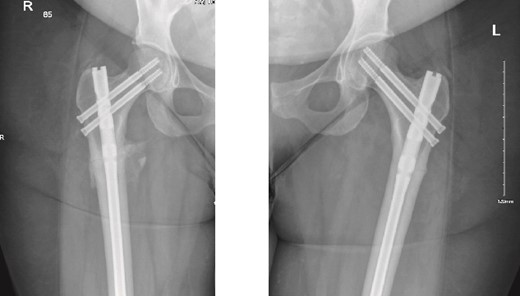

On examination, the patient was alert, oriented, and vitally stable. There were no open wounds on the right thigh, but mild tenderness was noted. The soft compartments were palpable, and the ankle range of motion was full. Distal neurovascular structures were intact. The left thigh showed no wounds or tenderness, and the hip range of motion was 0° to 60°, limited by pain in the right hip, as reported by the patient. Distal neurovascular structures were also intact on the left side. X-rays of both the right and left femurs, taken in the emergency department, are shown in Fig. 1.

Anteroposterior (AP) view of the right and left femurs pre-operative. With ismuths of 7.7 in R and 6.9 in L

Surprisingly, as seen in the X-rays in Fig. 1, the patient had a right subtrochanteric femur fracture and a stress line in the contralateral femoral cortex. While preparing and optimizing the patient for surgery, the endocrinology team was consulted regarding this presentation. According to their assessment, the patient’s laboratory findings were reassuring, and they confirmed that we could proceed with the surgical plan. Bone mineral density (BMD) testing was planned for afterward, and the endocrinology team would review the results. Surgery was scheduled for the following day.